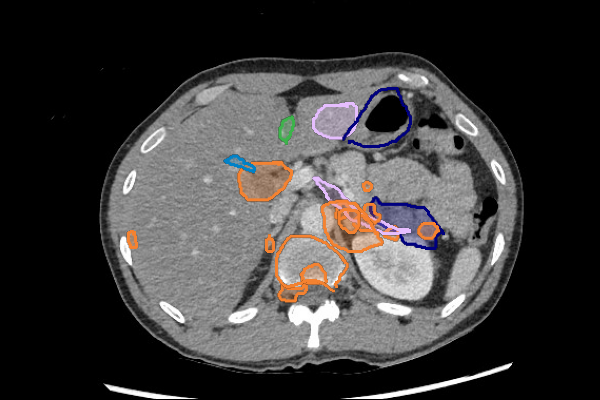

- Liver lesions can be subtle. Use a "Liver" window to increase sensitivity.

- Masses in the mesentery/peritoneum are often overlooked. Take advantage of multiplanar imaging and look in characteristic locations for peritoneal lesions.

- Kidney masses are also overlooked. Look carefully at the collecting system and for renal contour abnormalities.

Mass or Adenopathy

Infection or Inflammation

Thrombus

Slice 1

Slice 2

Slice 3

Slice 4

Slice 5

Slice 6

Slice 7

Slice 8

Slice 9

Slice 10

Slice 11

Slice 12